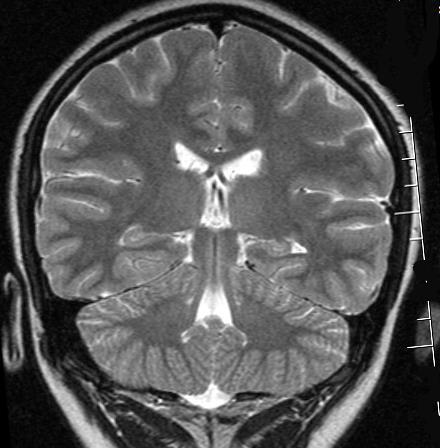

Dabrowski1,2, Martin Ndengera3, Felix T. Kurz1,4, Frédéric Grouiller1,2,3, et Sébastien Courvoisier1,2

Le mouvements en IRM contexte et solutions

L’IRM, technique d’imagerie médicale non invasive, est très sensible aux mouvements du patient car l’acquisition spatiale se fait de manière ségmentée. L’information complète requiert une séquence longue. En effet, l’IRM ne fait pas directement une image comme en rayon-X (RX ou CT-scan). En IRM, Le signal de résonance magnétique mesuré est enregistrée dans l’espace des fréquences spatiales appelé “espace-K”. L’image finale utilisée par les radiologue est obtenue par “reconstruction” via une transformation mathématique, la transformée de Fourier.

SISMIK le modèle de correction

Nous proposons un système de correction de mouvement rétrospectif sur les données de mesure IRM (espace-K) appelé SISMIK qui reconstruit des images avec moins d’artéfacts de mouvements.

Le système est dit hybride entre l’intelligence artificielle et les méthode algorithmiques plus traditionnelles, combinant les avantages des deux approches.

1. Les mesures “brutes” sont montrées à un réseau de neurones convolutionnel (CNN) entraîné au préalable.

2. le CNN estime pour chaque ligne d’aquisition le déplacement relatif effectué par rapport au lignes adjacentes.

3. le réseau produit une trajectoire complètes (mouvement dans le temps) le long de l’acquisition

4. la trajectoire et les données brutes sont envoyées au second algorithme afin qu’il corrige et reconstruise les images correspondantes.

Notre méthode est dite rétrospective (appliquée après la mesure) et basée sur la technique IRM exclusivement. Ses avantages sont les suivants:

▪ Aucune modification des séquences cliniques usuelles (des modifications rendraient les séquences non-standard et nécessitent un développement et une validation spécifique pour chaque constructeur/marque IRM).

▪ Pas de séquence additionelle nécessaire, la référence du mouvement est relative et contenue dans l’acquisition

▪ Aucun équipement supplémentaire ou externe est nécessaire.

▪ Polyvalent au contrastes IRM (T1w, T2w démontré) et au contenu (théorique, à tester). C’est à dire que par exemple le réseau de neurone peut être entrainé sur des données IRM réalisé avec un contraste T1w acquis sur des objets comme des fruits mais appliqué à des cerveaux et en contrastes T2w